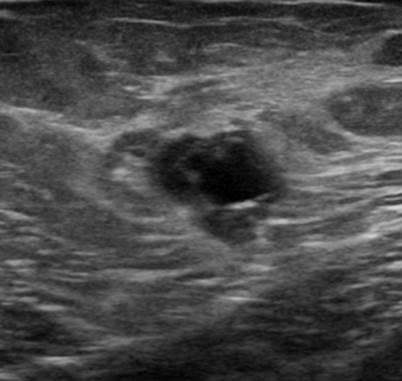

Ung thư vú

Ung thư vú - Ảnh 2

» Thông tin: Nữ giới – 50 tuổi.

» Lâm sàng: Kiểm tra sức khỏe.